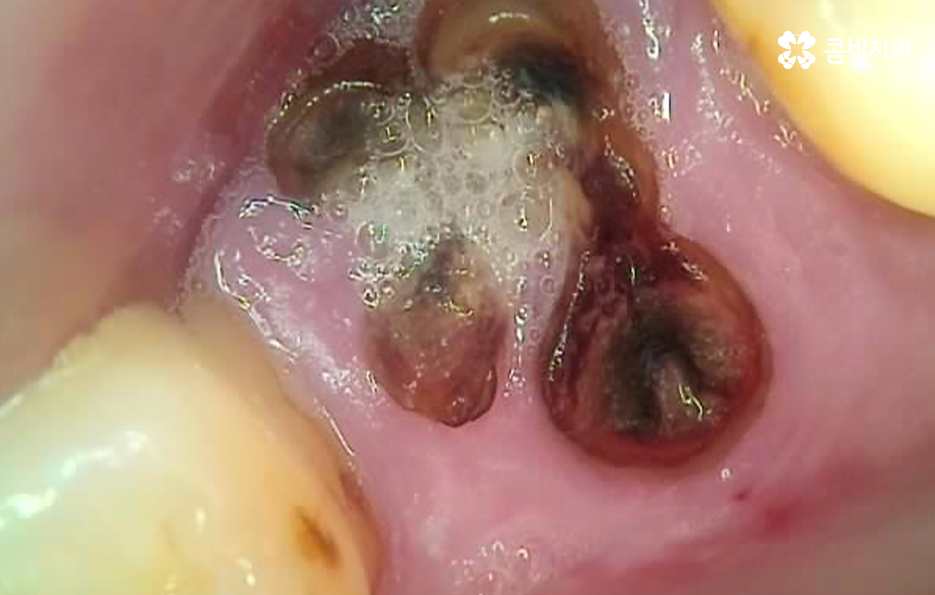

위 사진을 보시면 치아 자체의 노화나 균열도 물론 크지만 잇몸이 내려앉아서 치아의 뿌리 부분이 외부에 노출되어 있는 것을 알 수 있는데요. 노인임플란트 필요로 하는 분들의 치아 상실의 대표적 원인은 충치 부터 오래된 크라운, 치아의 손상 및 균열로 인한 문제도 크겠지만 결정적으로는 치주염으로 인해 잇몸 뼈가 녹고 잇몸 퇴축으로 인한 치아 상실이 노년기에 발생하는 치아 상실의 대표적 원인이 되고 있어요

위 케이스의 노인임플란트 치료의 경우 치아의 균열부터 뿌리까지 깊어진 충치, 치주염 까지 복합적인 이유로 치아를 상실하고 여러 개의 임플란트를 식립한 사례라고 할 수 있는데요. 그래도 아직은 잔존하고 있는 치아가 많기 때문에 이미 상실한 치아에는 노인임플란트 각 위치에 맞게 적절한 치료를 받고 나머지의 자연치아에 대해서는 잘 관리하는 것이 중요한 시점이라 할 수 있어요

실제 노인임플란트 치료 사례를 보면 치아의 대부분을 잃고 전체 임플란트를 해야 하는 사례가 많고 치아를 하나둘씩 잃게 되는 시점에 좀더 잇몸 관리를 잘했더라면 유지가 되었을 잇몸 뼈의 건강도 치주염으로 인해 잇몸 뼈의 소실로 이어지는 사례가 많아 뼈이식이나 상악동거상술과 같은 추가적인 술식으로 이어지는 사례가 많이 있는데요